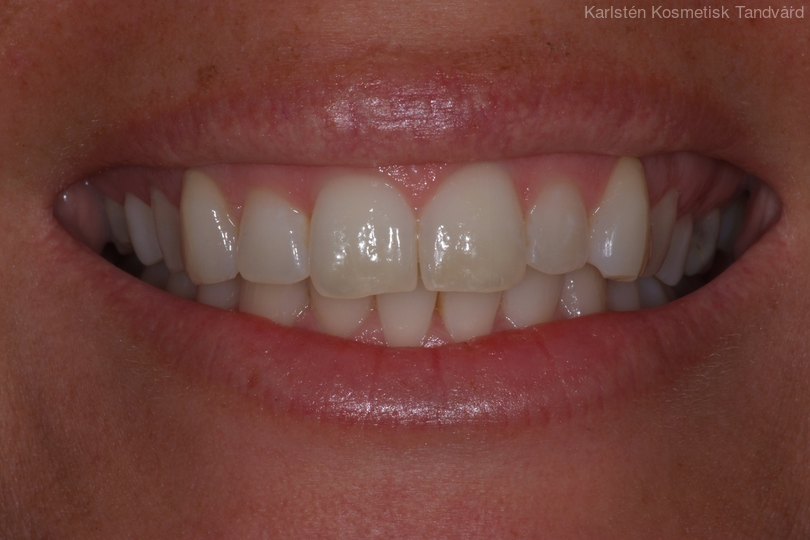

Tandreglering 4

40-årig kvinna som tycker att de två framtänderna står ut framför alla andra tänder. Behandlingen bestod av 11 månader med genomskinliga Invisalignskenor.